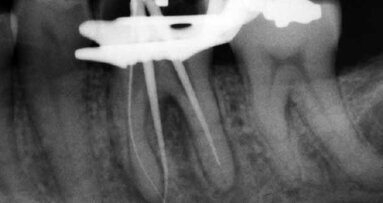

As a practicing endodontist over the past 25 five years, you believe you’ve seen whatever can walk in the door case wise. We are taught to look at ...